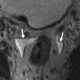

Peritoneal fluid

Peritoneal fluid is a serous fluid made by the peritoneum in the abdominal cavity which lubricates the surface of tissue that lines the abdominal wall and pelvic cavity. It covers most of the organs in the abdomen. [Source: Wikipedia ]